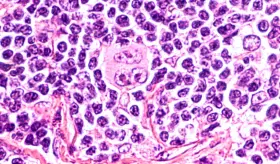

En distintos países se están desarrollando terapias innovadoras (inmunoterapia, CAR-T, vacunas terapéuticas, terapias dirigidas y reprogramación celular) que muestran resultados alentadores. Sin embargo, la mayoría se encuentra en fases preclínicas o ensayos clínicos temprano